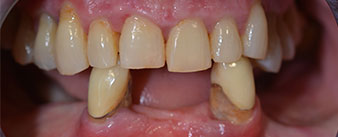

Die 64-jährige Patientin wurde mit einer Unterkiefer-Restbezahnung 38, 33 und 43 und einer klammerbefestigten Interimsprothese im Unterkiefer vorstellig (Abb. 1 und 2).